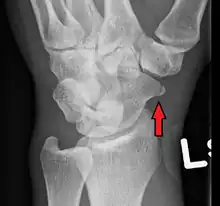

A subtle scaphoid fracture

A more obvious scaphoid fracture on a scaphoid view X ray

Radiolucency around a 12 days old scaphoid fracture that was initially barely visible.[13]